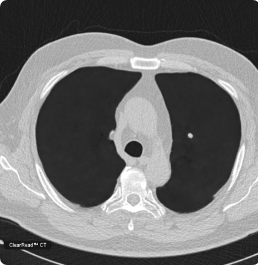

ClearRead CT with Clear Visual Intelligence provides an unimpaired view of the chest for efficient and accurate detection of cardiothoracic diseases. The full suite of tools detects, segments, and measures nodules, compares findings with prior exams, quantifies CAC, and automatically integrates with the radiology report. ClearRead CT is a natural addition for opportunistic CAC and nodule detection or as part of a lung cancer screening program. Detect 29% more nodules and read 36% faster.2,14